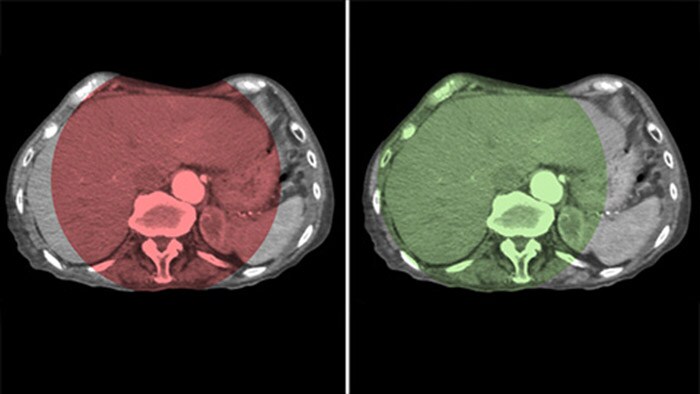

THC Dual permite la adquisición de imágenes en 3D de una fase arterial para visualizar estructuras vasculares y una posarterial (fase retardada) para ver la acumulación del medio de contraste, en un solo paso automático.5

Dual View permite la visualización simultánea de dos conjuntos de datos de la THC. Tanto la fase arterial como la retrasada se pueden mostrar una al lado de la otra o en una sola vista de superposición fusionada.

Dual View permite ver de forma simultánea la imagen 3D de la fase arterial antes de la embolización y la imagen después de la embolización para evaluar el fin del tratamiento.